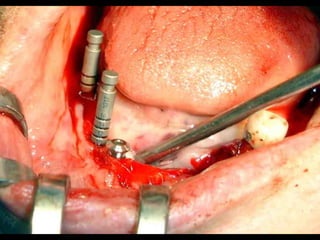

Primer tiempo quirúrgico; Exposición del maxilar para tomar una impresión del

hueso y poder elaborar la estructura implantaria.

Primer tiempo quirúrgico;Exposición del maxilar para tomar una impresión del hueso y poder elaborar la estructura implantaria.

Exposición del maxilarpara tomar la impresión